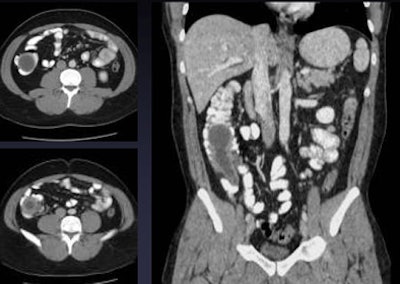

| Tumors can cause obstructive appendicitis, especially in elderly populations, as in the cecal cancer, above, causing acute appendicitis. Below, alternative diagnosis of an intussuscepted appendicele. All images courtesy of Dr. Perry Pickhardt. |